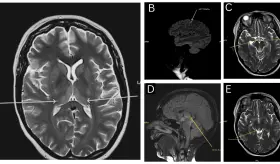

Este caso destaca la importancia de considerar etiologías supratentori...

La resonancia reveló un infarto "puntiforme" en la unión parieto-occipital, región involucrada en la percepción de verticalidad y orientación espacial, explicando la ilusión vestibular sin otros déficits neurológicos evidentes.

Los hallazgos en resonancia magnética mostraron el patrón característico de edema vasogénico en regiones parieto-occipitales bilaterales.